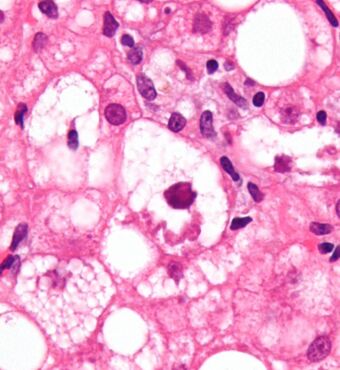

| Micrograph showing a Mallory body, a histopathologic finding associated with alcoholic hepatitis. H&E stain. |

- Mallory's hyaline body – a condition where pre-keratin filaments accumulate in hepatocytes. This sign is not limited to alcoholic liver disease, but is often characteristic.[6]

- Ballooning degeneration – hepatocytes in the setting of alcoholic change often swell up with excess fat, water and protein; normally these proteins are exported into the bloodstream. Accompanied with ballooning, there is necrotic damage. The swelling is capable of blocking nearby biliary ducts, leading to diffuse cholestasis.[6]

- Inflammation – neutrophilic invasion is triggered by the necrotic changes and presence of cellular debris within the lobules. Ordinarily the amount of debris is removed by Kupffer cells, although in the setting of inflammation they become overloaded, allowing other white cells to spill into the parenchyma. These cells are particularly attracted to hepatocytes with Mallory bodies.[6]